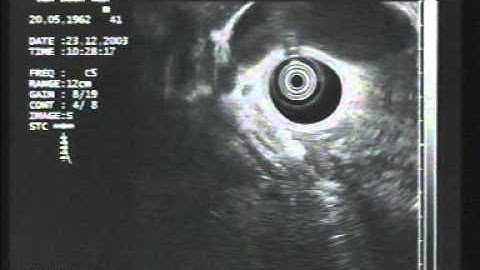

EUS sampling of suspected cholangiocarcinoma